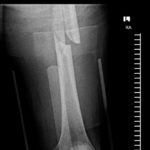

Vor ein paar Stunden wurde Steve deswegen im Palomar Medical Center Escondido operiert. Wie er selber berichtet, ist bei der OP an seinem Spiralbruch, linker Oberschenkel, alles perfekt abgelaufen.

An den Fotos unten kann man gut erkennen, dass der Knochen nun durch ein Titanstück und zwei Schrauben zusammengehalten wird. Den Moment des Sturzes hat Caballero auf Instagram hochgeladen. Den Clip findet ihr unter den Fotos.